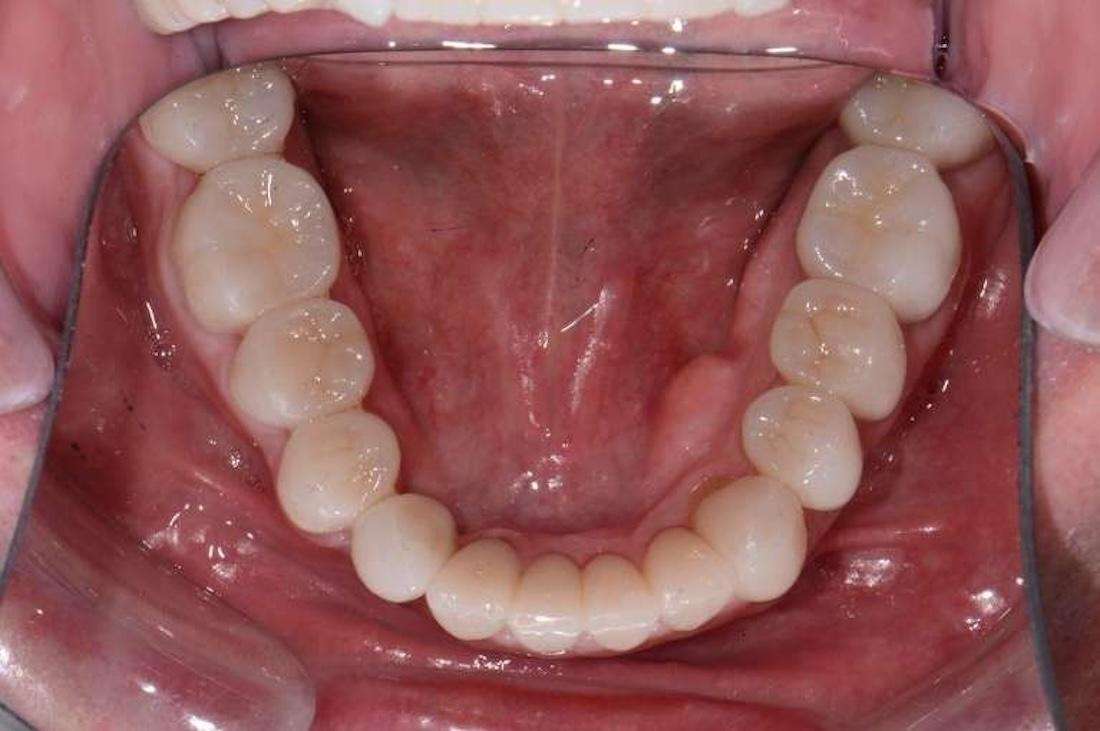

Upper and Lower Porcelain Crown Full Mouth Reconstruction (28 Teeth).

At first, I tried conservative bonding on the upper front teeth, but it simply could not hold up against the patient’s bite issues. After careful planning, I completed a full mouth reconstruction with porcelain crowns. This allowed me to open and correct the bite, restore proper function, and dramatically improve the aesthetics. The final result was a balanced, healthy, and natural-looking smile that gave this patient their confidence back. I especially enjoyed this case because it demonstrates that complex, full mouth reconstructions are not limited to prosthodontists. With advanced training, a general dentist like myself can achieve outstanding results for even the most challenging cases.